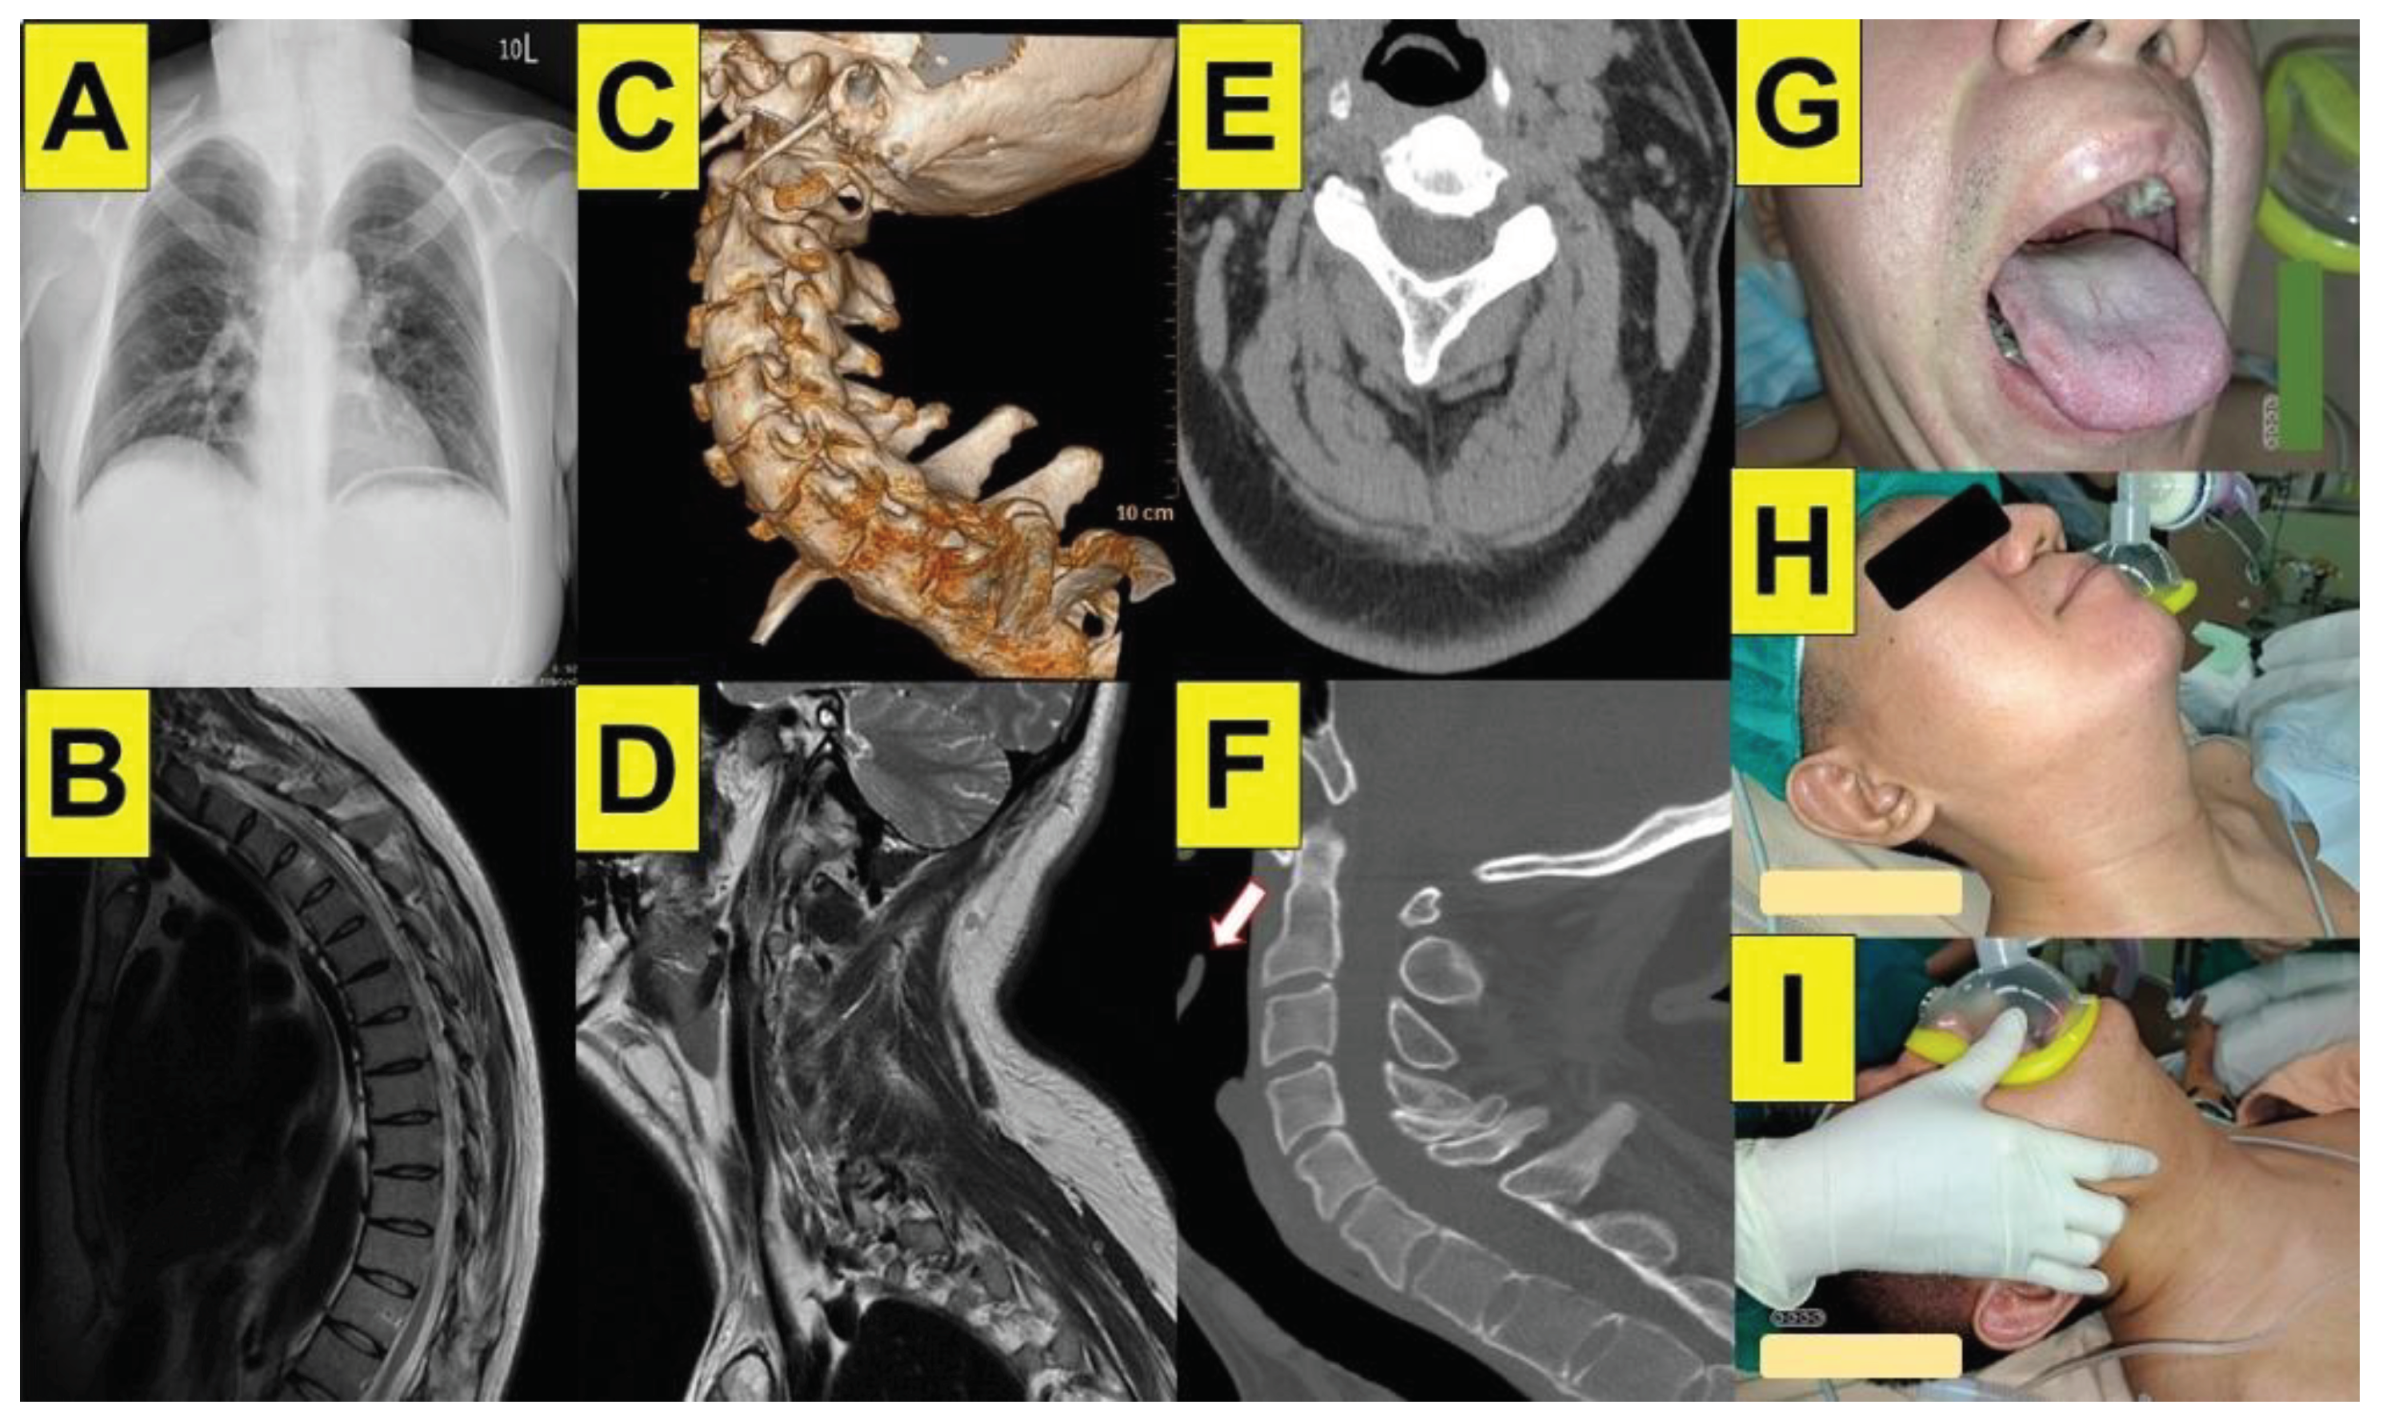

One of the examples of severe degree of limited cervical spine motion is the case of ankylosing spondylitis (AS). In few sporadic case reports, the roles of different intubating tools have been studied in patients with AS [120,121,122], including combined VL with video stylet [123]. Here, we present a case of AS undergoing corrective orthopedic spine surgery (Figure 9). The patient has past history of ankylosing spondylitis with severe cervical hyperlordosis, and progressive thoracic kyphosis. Orthopedic operation included pedicle subtraction osteotomy (PSO), posterior instrumentation (PI), posterior lumbar interbody fusion (PLIF). His cervical mobility was severely restricted. After careful assessment was performed, we applied styletubation for tracheal intubation under standard induction of anesthesia. The time to intubationis 16 s with first-pass success (Figure 10).

Cricoid pressure (CP) did not significantly improve the glottic visualization at laryngoscopy but increased the time to intubation significantly decreased the first-pass success rate [135]. Recent large randomized clinical trial performed in patientsundergoing anesthesia with RSII failed to demonstrate the non-inferiority of the non-CP procedure in preventing pulmonary aspiration [144]. Therefore, we routinely abandon CP (or Sellick maneuver) while applying styletubation for rapid sequence induction/intubation (RSII). Here we present a case of using styletubation for RSII (Figure 12). This is a 59-year-old man with past history of atrial fibrillation, hypertension, ankylosing spondylitis (with stiff neck and limited cervical spine mobility), and deep vein thrombosis. He was admitted to our emergency room due to cerebellar hemorrhage and scheduled for emergent suboccipital decompressive craniectomy with intracranial pressure monitoring. Anesthetic induction agents were administered for RSII. The styletubation took only 9 s to complete with first-pass success. No CP was applied.